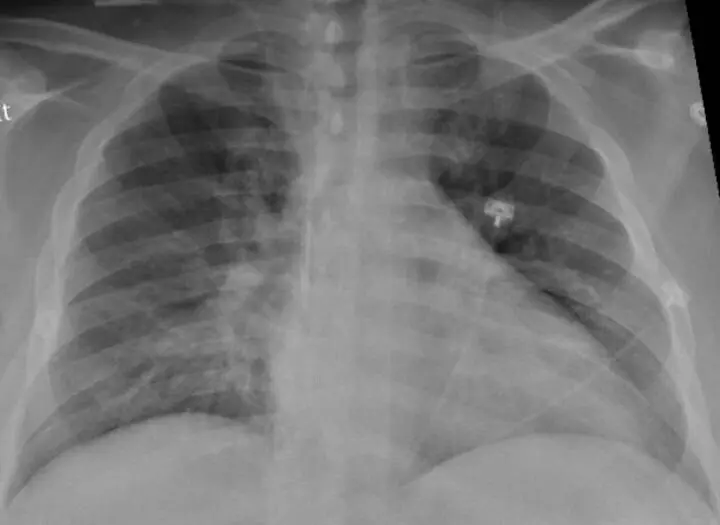

Archivo - La radiografía de tórax de un paciente positivo de COVID-19 que muestra una neumonía en la parte inferior de los pulmones.